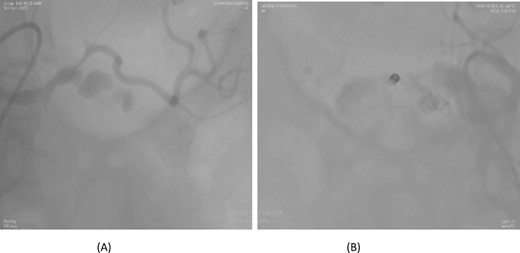

A 66-year-old male underwent an extended cholecystectomy with bile duct excision and Roux-en-Y hepaticojejunostomy for suspected gallbladder carcinoma. However, the histopathological examination revealed xanthogranulomatous cholecystitis. Postoperative patient develops anastomotic site leakage so was discharged with abdominal drain. On the 9th postoperative day, during follow-up for bile leak with an abdominal drain in situ, a contrast-enhanced CT scan of the abdomen identified a pseudoaneurysm at the bifurcation of the gastroduodenal artery and proper hepatic artery. Angioembolization was performed using two coils and 50% glue. The abdominal drain was subsequently removed, and the patient recovered without further complications, doing well at follow-up (Fig. 4).

Case 4. (A) CT scan – pseudoaneurysm at bifurcation of gastroduodenal artery and proper hepatic artery. (B) Embolization of gastroduodenal artery and proper hepatic artery.